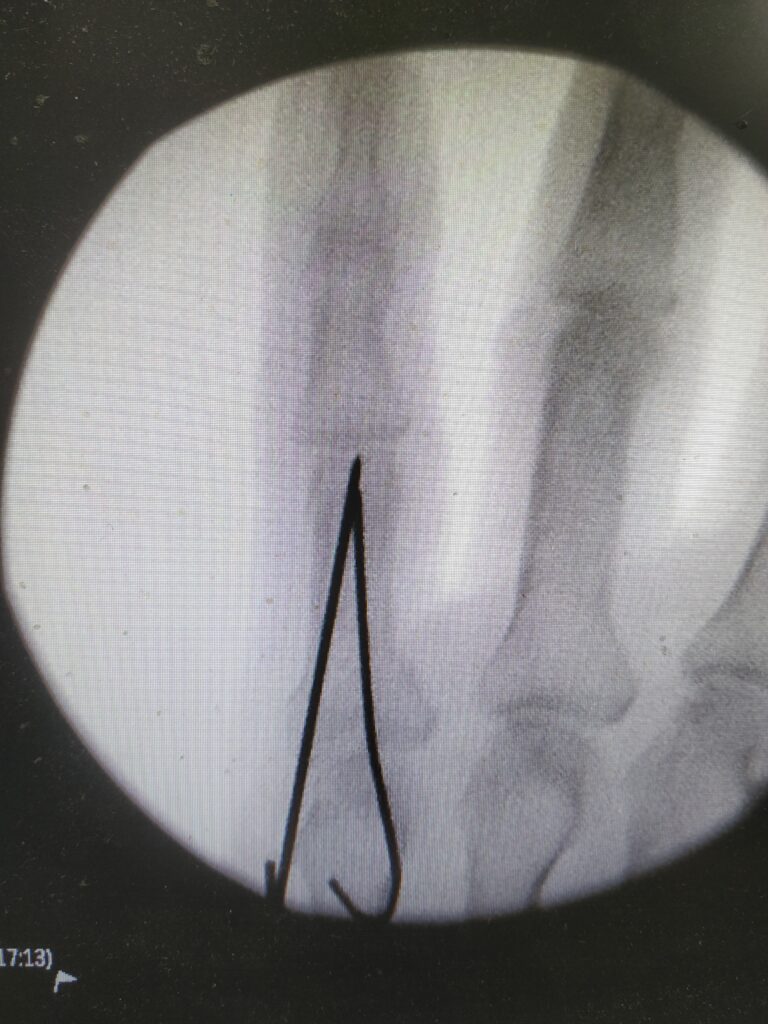

What does a hand fracture surgery involve?

The objective of hand fracture surgery is to achieve fixation of the broken bone segments with as minimum manipulation or dissection as possible. This is most instances can be achieved with K wires which are simply stainless steel nails drilled through the skin across the fracture site. This modality is widely practiced , remains least invasive and can be modified as per most fracture configurations

Of course, your surgeon may suggest screw fixation or plating if your fracture is more complex or not amenable to K wiring and very rarely external frames like distractors for more complex situations.